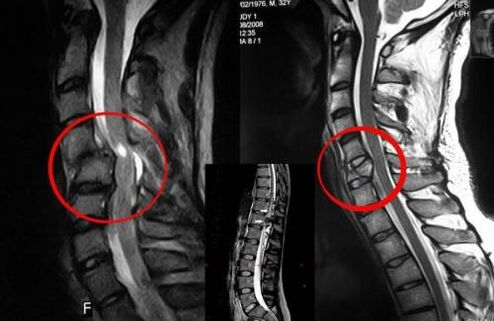

Diagnostiek

Wervelosteochondrose vereist tijdig overleg met een arts die zal helpen de beschadigde rug te herstellen. Moderne apparatuur maakt het mogelijk om al in een vroeg ontwikkelingsstadium een diagnose te stellen. Neem in geval van pathologie contact op met een neuroloog of orthopedist. Eerst wordt een onderzoek van de gewonde wervelkolom uitgevoerd en een medische geschiedenis afgenomen, waarna laboratorium- en instrumentele diagnostische methoden worden voorgeschreven die osteochondrose identificeren:

- röntgenfoto;

- myelografie;

- neurologisch onderzoek;

- CT en MRI;

- nucleaire magnetische resonantie.